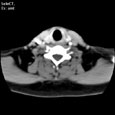

Критический стеноз правой внутренней сонной артерии. Критический стеноз правой внутренней сонной артерии

Пациент U., 69 лет

Критический стеноз правой внутренней сонной артерии.

ЦКБ5 Южной железной дороги, отделение лучевой диагностики.

На КТ-сканах шеи (до уровня основания черепа) в условиях ангиографического режима (в/в ультравист 300 - 100,0 мл 2,5 мл/сек.) определяется окклюзия правой внутренней сонной артерии на 15 мм дистальнее бифуркации общей сонной артерии, дистальнее контрастирование просвета артерии не определяется. Ассиметрично контрастированы яремные вены (справа интенсивность контрастирования значительно ниже).